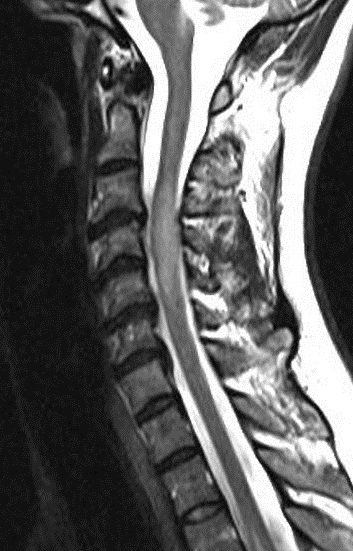

A MRI scan of brain and spine showed increased T2 signal and expansion of the cord in some areas of the spinal cord at the levels of C2–C5, and C7 to T12. The patient was given methylprednisolone 1 gram intravenous for a period of 5 days and oral steroids for 4 weeks. Thyroid function tests were reported to be normal (Table 3 [Tab. 3]). The patient showed marginal improvement in vision and reduction of sensory abnormalities by about 50% over a period of 6 weeks. In April 2015, the patient was admitted with cough associated with mucopurulent expectoration, shortness of breath, paraesthesias and diminished vision. The patient showed minimal improvement in sensory symptoms or vision. In May 2015, the patient was admitted with progression of bilateral lower limb weakness, bilateral upper limb weakness (distal > proximal) and a band-like sensation around the chest, syncope, vomiting and hiccups. Clinical examination revealed normal higher mental functions with diminished vision to finger counting in the right eye. Other cranial nerves were normal.

Immunological tests for ANA titer were 1:320, tests for anti-ENA, anti-dsDNA, anti-cardiolipin, anti-β2GPI, lupus cells, antibodies to GAD65, IA-2, insulin and cryoglobulins were negative. MRI brain and whole spine revealed 1) hyperintensity in cervical cord C5 to C7 level (Figure 1 [Fig. 1], Figure 2 [Fig. 2], Figure 3 [Fig. 3]); 2) hyperintensity in the thoracic cord till T12 level (Figure 4 [Fig. 4], Figure 5 [Fig. 5], Figure 6 [Fig. 6]); 3) hyperintensity in the right optic nerve head (Figure 7 [Fig. 7]). The clinical features and investigations (NMO IgG was positive) fit into the criteria of neuromyelitis optica. The thyroid profile was suggestive of hypothyroidism (Table 3 [Tab. 3]). Laboratory studies confirmed the presence of antithyroid antibodies (Table 4 [Tab. 4]). Fine needle aspiration of the thyroid showed lymphocytic infiltration of the thyroid gland (Figure 8 [Fig. 8], Figure 9 [Fig. 9]). The patient was treated with prednisolone 1 g/day for 5 days and azathioprine (2.5–3 mg/kg/daily). The patient showed improvement in motor symptoms and sensory symptoms approximately by 60% after a period of 2 months of treatment. Patient was started on thyroxine 50 μg and later dosage was increased to 100 μg.

Figure 1: MRI spine showing hyperintensity in cervical cord C5 to C7 level (1)

Figure 2: MRI spine showing hyperintensity in cervical cord C5 to C7 level (2)

Figure 3: MRI spine showing hyperintensity in cervical cord C5 to C7 level (3)